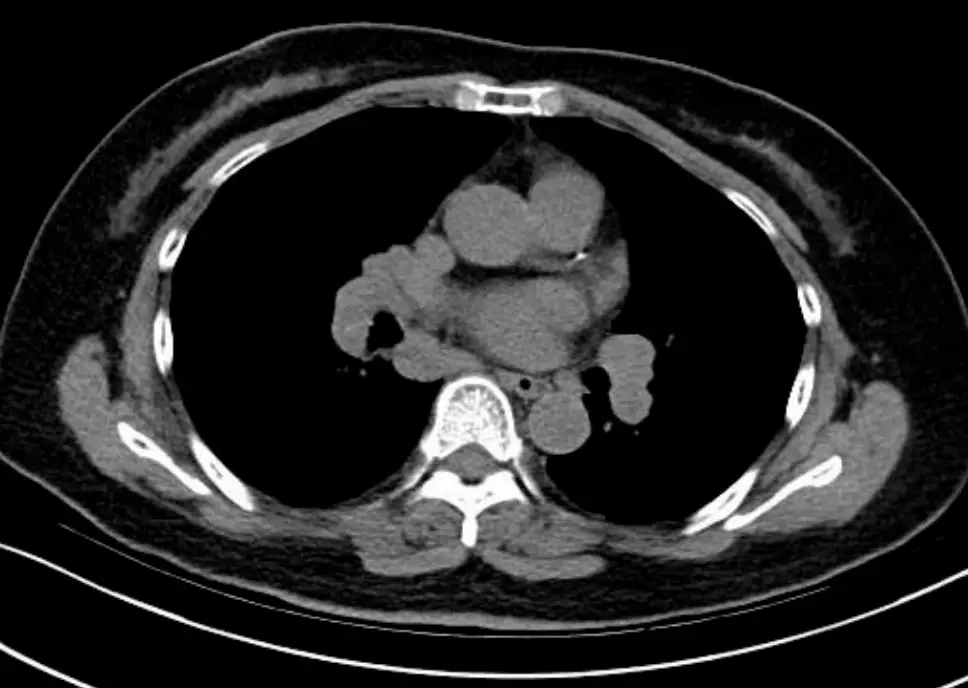

- CT橫截面影像(上段、中央):

- 在肺門及縱隔區域,淋巴結明顯腫大,形態規則、邊界完整、密度均質,無中央壞死或環形增強。

- 肺實質可見多發性微小結節,沿支氣管血管束分佈(peribronchovascular distribution),並可見部分結節沿間質(interlobular septa)與胸膜下區域延伸,呈現「經淋巴路徑分佈」(perilymphatic)特徵。

- 無單一實質腫塊、無大範圍實變或空洞。